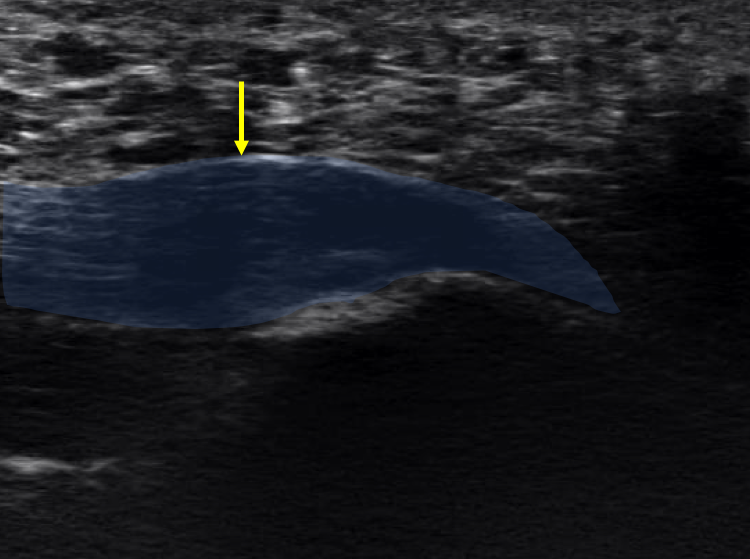

例)足底腱膜炎

足底腱膜の変性(腫れ)の評価(矢頭)

当グループでは超音波診断装置を用いて注射を行っています。

レントゲンやMRI、超音波診断装置でどこが病因なのかを探りその部位に注射を行います。

その際に関節内が問題な場合は関節内に注射を行い、腱周囲や腱付着部が問題の場合は腱周囲や腱付着部に注射を行います。

腱周囲や腱付着部に抗炎症剤を含めた薬液で注射を行い炎症の抑制を目的に行います。